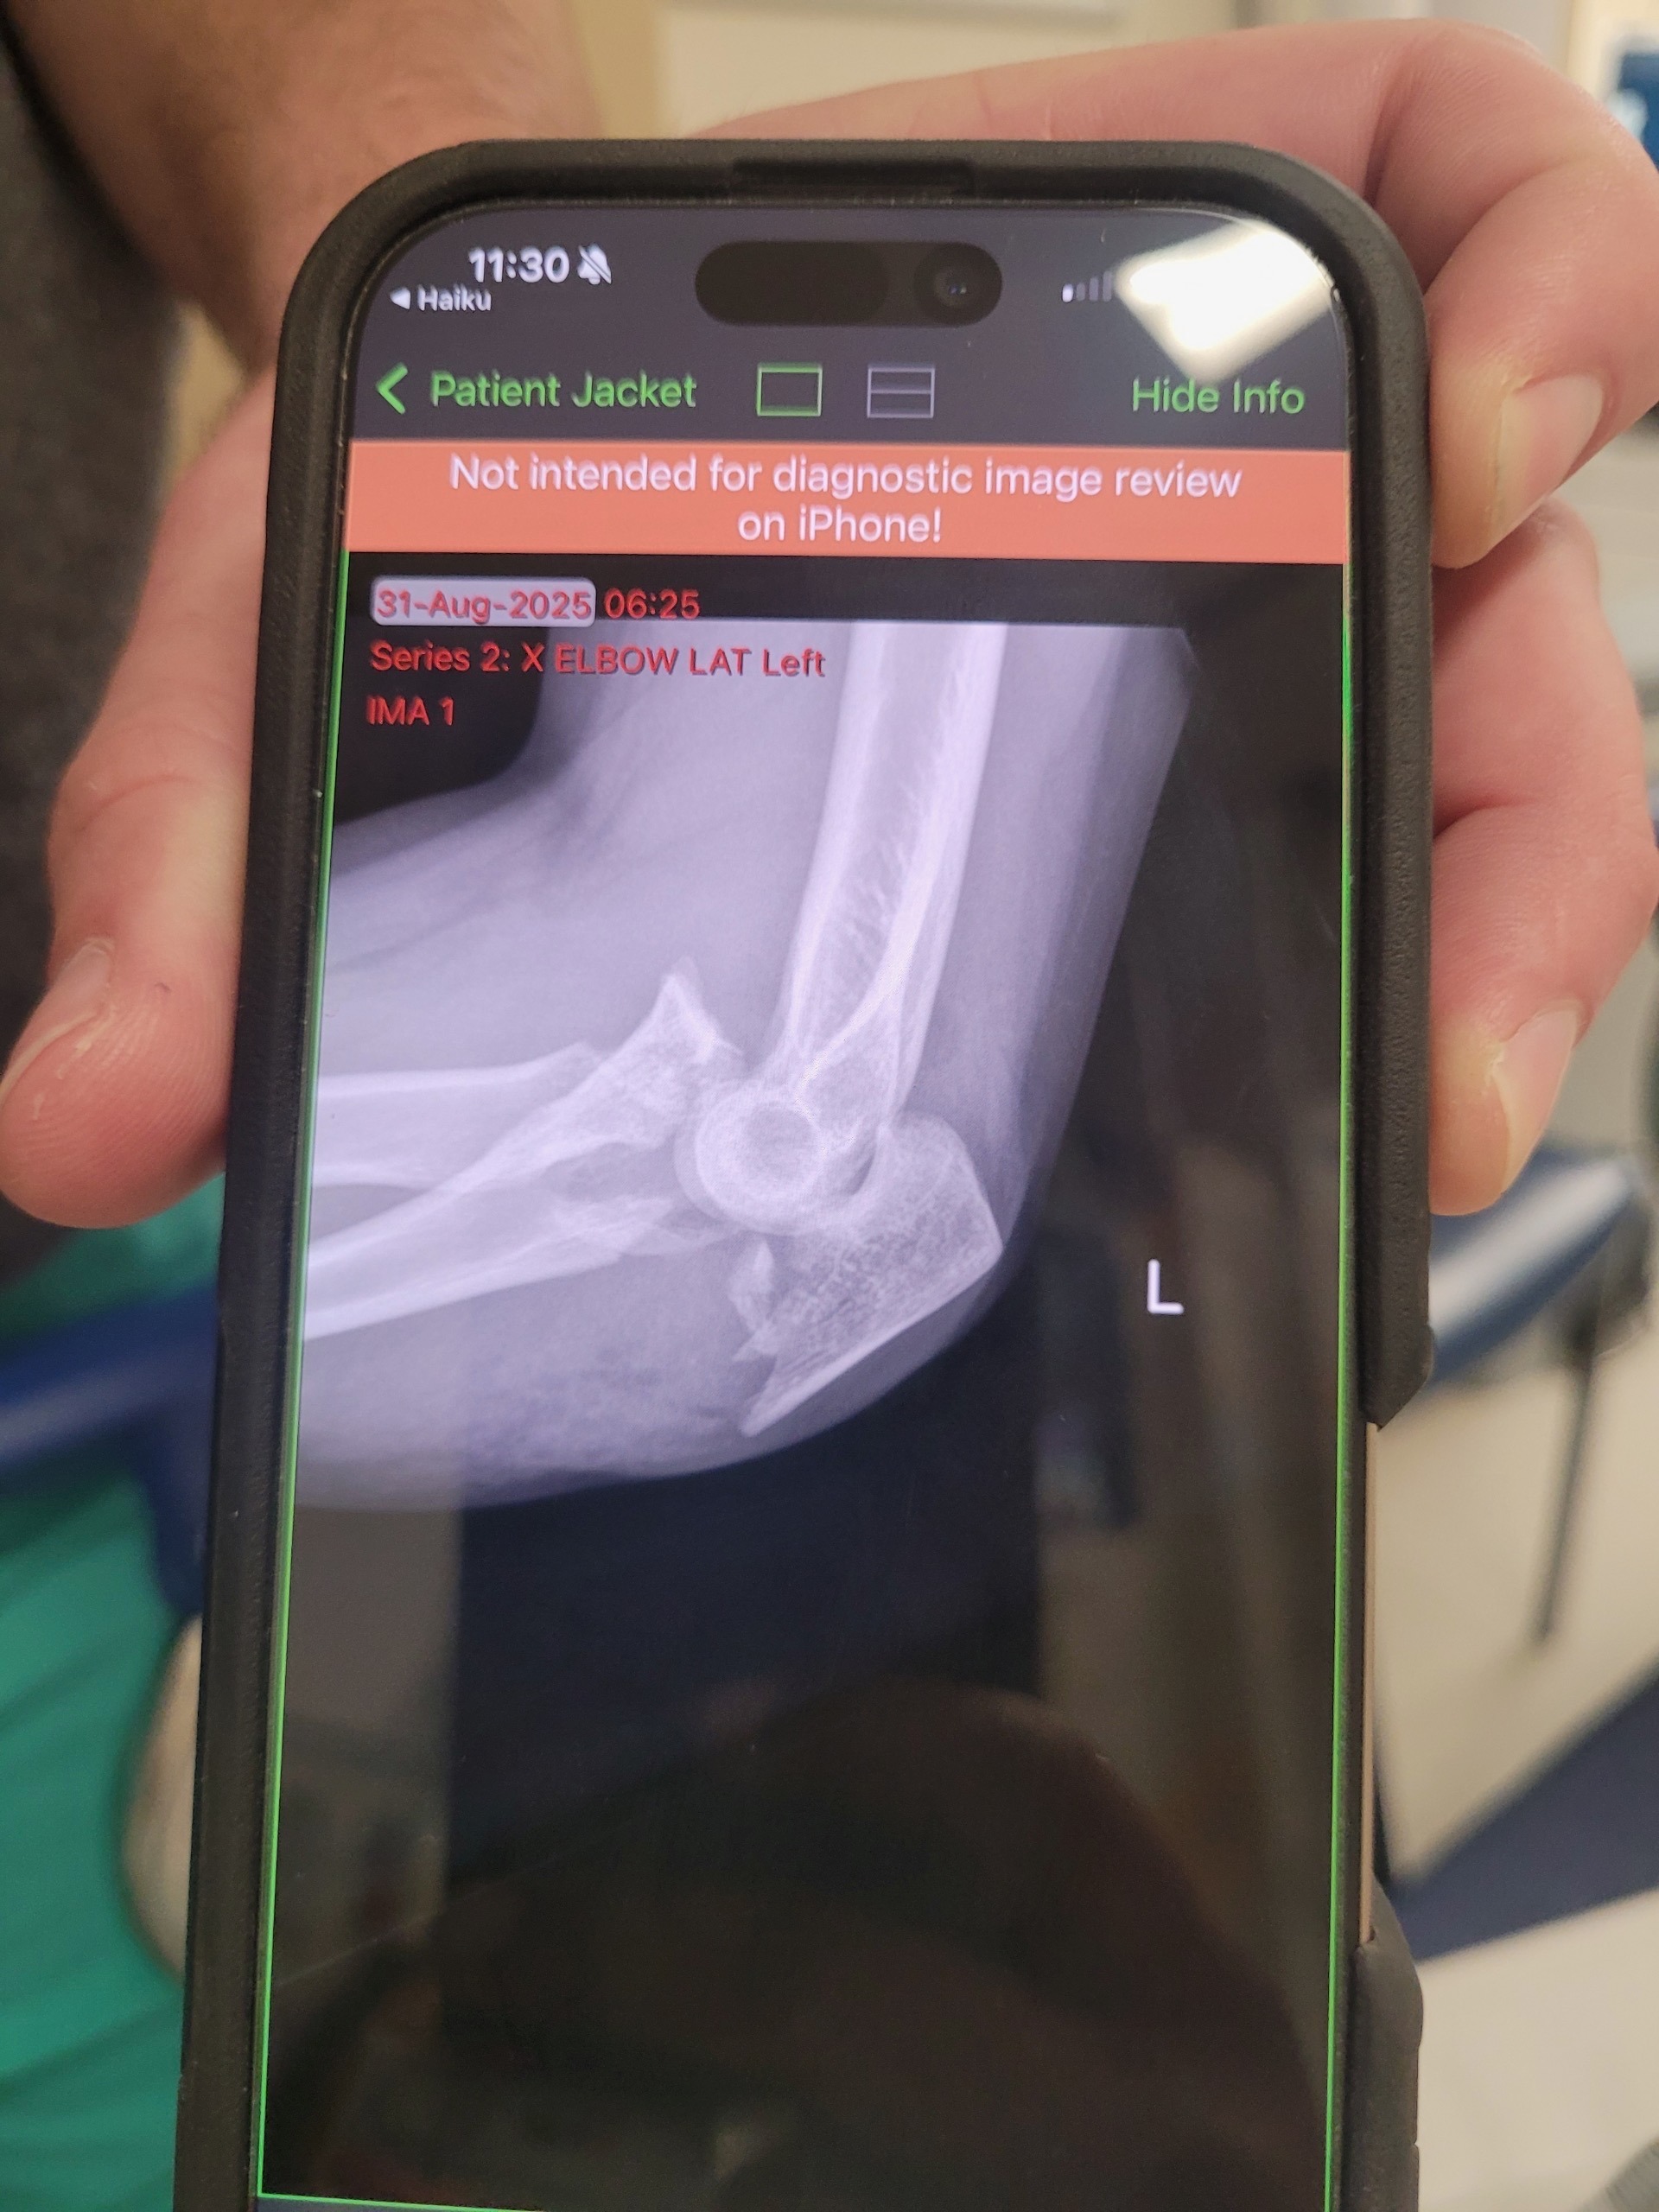

On Saturday morning, August 31st, Luna was on her way home from work when two cars forced her off the road while she was riding her scooter. The accident caused a severe fall that left her with a broken left elbow and a fractured right shin.

A good Samaritan found her at the scene and assisted her to her house, until the ambulance arrived. Luna was rushed to the hospital, where she underwent an 8-hour emergency surgery on her elbow and leg.